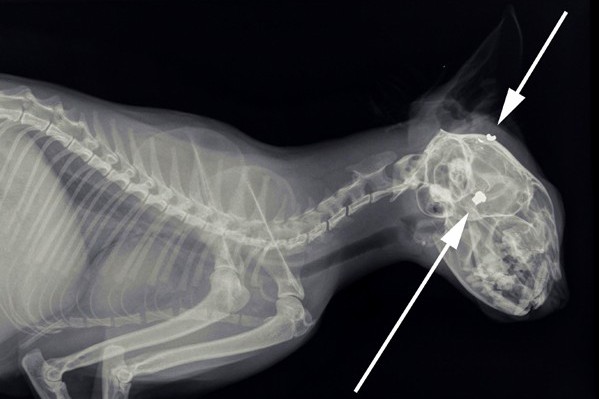

In de nacht van 14 op 15 november werd er bij de Dierenambulance een overleden kat aangeboden, die in een achtertuin in Maurik was gevonden. Het diertje, wat verder in zeer goede conditie leek te zijn, had een klein rond gaatje achter het rechter oor. De Dierenambulance bracht de kat bij onze dierenarts om een röntgenfoto te laten maken. Hiermee konden we vaststellen of het dier beschoten was. Een wondje zoals deze kat liet zien betekent namelijk niet automatisch een kogelgaatje. Zoals op de foto te zien is, is er dus inderdaad een kat beschoten in Maurik. In de schedel zijn één kogel en één kogelfragmentje aanwezig.